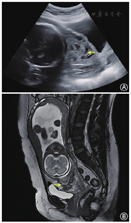

(1)1例CSP-Ⅰ型患者,既往有反复着床失败病史,卵巢功能减退,超声评估子宫下段剖宫产切口部位残余肌层厚度5 mm,患者及家属有强烈继续妊娠意愿,经全科病例讨论及充分医患沟通,采取期待治疗。产检筛查超声反复提示凶险性前置胎盘伴胎盘植入,孕31+周因羊水过少行剖宫产+手取胎盘+子宫下段宫颈提拉式缝合+双侧子宫动脉下行支结扎+子宫B-lynch缝合术,术中出血2 100 ml,新生儿出生体重1 430 g,1分钟Apgar评分9分,5分钟Apgar评分10分,经新生儿重症监护室(NICU)治疗后出院,现体健。(2)2例HCSP患者均为CSP-Ⅱ型,接受经阴道剖宫产瘢痕部位妊娠囊穿刺抽吸减胎术,术中于妊娠囊局部注射高渗葡萄糖溶液进一步减灭妊娠组织。其中1例患者孕中晚期产科超声及磁共振成像(MRI)反复提示妊娠组织完全性前置伴植入(图1),于孕29+周因产前出血行剖宫产+手取妊娠组织+子宫下段间断8字缝合+双侧子宫动脉下行支结扎+子宫B-lynch缝合术,术中出血3 200 ml,术后病理示前置伴植入的妊娠组织为梗死退变的胎盘组织。新生儿出生体重1 450 g,1分钟Apgar评分7分,5分钟Apgar评分9分,经NICU治疗后出院,现体健。另1例患者未于本院建档产检,经随访获知患者于孕35+周因"前置胎盘伴产前出血"行剖宫产术,新生儿出生体重3 000 g,现体健。(3)1例CSP-Ⅲ型患者行腹腔镜盆腹腔粘连松解+子宫瘢痕妊娠组织清除+子宫修补术,术后15个月时第1次胚胎移植(解冻周期单囊胚移植),早孕期超声提示正常宫内妊娠,孕期平顺,孕37+周经剖宫产术分娩,新生儿出生体重3 450 g,现体健。(4)24例CSP-Ⅰ型或Ⅱ型患者行宫腔镜子宫瘢痕妊娠组织清除术±子宫动脉栓塞术。其中22例(91.7%)患者首次宫腔镜手术治疗成功,术后1~2个月血β-hCG降至<5 mU/ml;其余2例(8.3%)患者因持续性CSP再次行宫腔镜子宫瘢痕妊娠组织清除术。4例患者术后10~18个月历经1~2次移植周期获得临床妊娠,均妊娠至足月经剖宫产术分娩,无再发性CSP(RCSP)、胎盘植入、子宫破裂、产后出血、新生儿窒息等严重并发症。6例患者术后10~48个月历经1~3次移植周期未获临床妊娠,无再妊娠意愿。其余14例患者目前仍处于辅助生殖助孕治疗周期中。

HCSP则是CSP中更为少见的类型之一,本研究中HCSP累计发病率为0.14%(2/1 441),在CSP中占7.1%(2/28),低于Ouyang等[19]报道的50%(6/12),考虑与本中心平均移植胚胎数较低有关(1.43枚比2.08枚)。HCSP的治疗以减灭CSP并保留宫内妊娠为主要目的。由于甲胺蝶呤(MTX)对宫内妊娠有潜在致畸作用,减胎局部用药以氯化钾或高渗葡萄糖更为常用[20]。然而,尽管妊娠已被终止,但瘢痕部位的妊娠滋养组织难以实现完全减灭,如本研究中病例所示,残留妊娠组织继续侵袭并发植入,最终导致早产及产后出血。因此,HCSP经阴道选择性减胎术后仍需严密随访、准确评估、充分准备。本研究局限性在于样本量较小,今后需开展更大样本量的队列研究及随机对照研究,对相关发现做进一步验证。